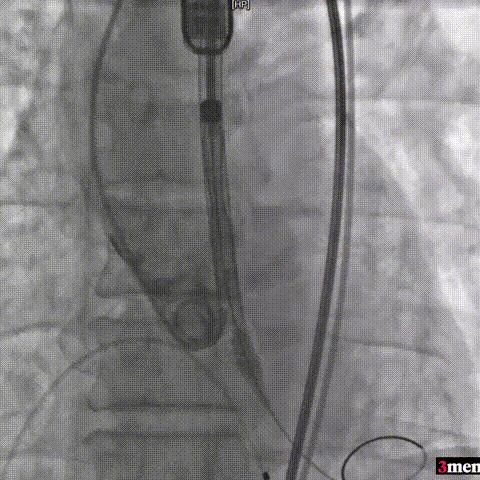

手术过程回顾:

主动脉根部造影

直头导丝跨瓣

球囊预扩

输送器过弓

瓣膜定位

瓣膜释放至工作位

瓣膜脱钩

球囊后扩

术后超声提示患者跨瓣压差即刻显著下降,反流量轻微。术中未出现相关并发症,术后患者心功能持续得到改善,效果良好,圆满取得此次手术成功。